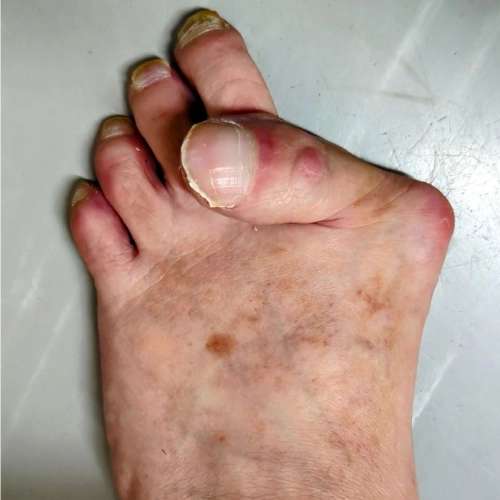

Tailor’s bunion treatment for pain and deformity on the outer side of the footTailor’s bunion treatment for pain and deformity on the outer side of the foot

Bunion treatment to correct toe alignment and relieve foot painTailor’s bunion treatment for pain and deformity on the outer side of the foot

Tailor’s bunion treatment for pain and deformity on the outer side of the foot06-